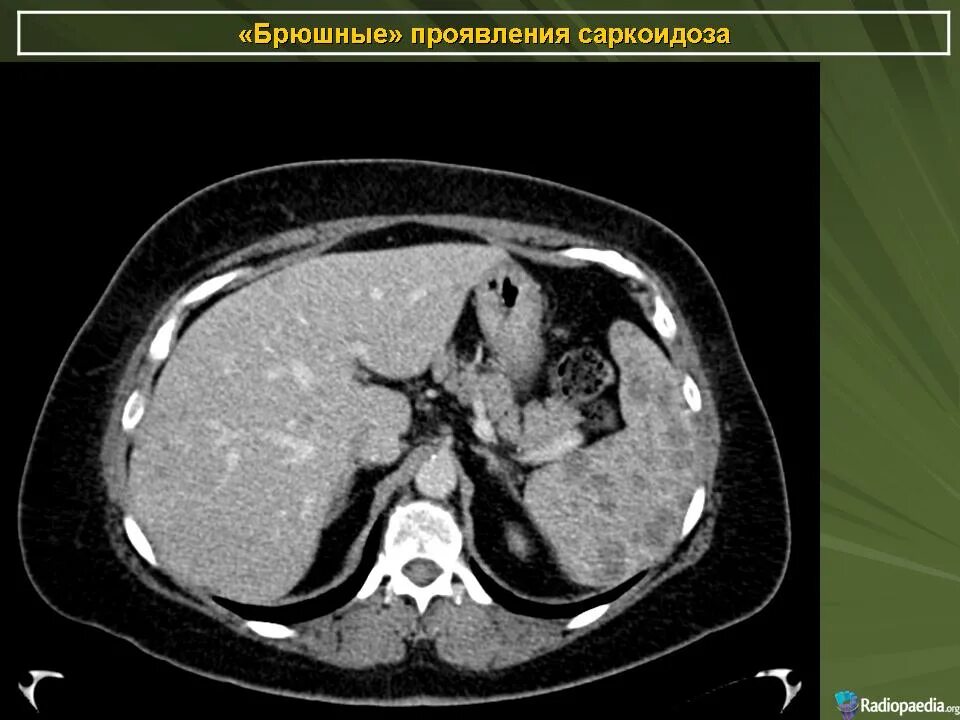

Диффузные изменения печени кт